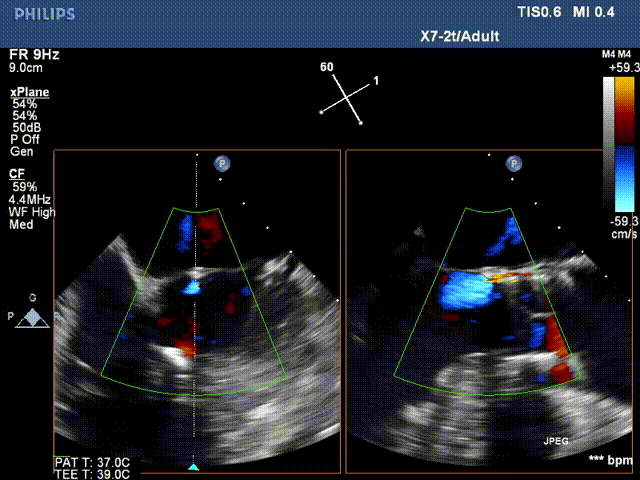

术后超声:

术后超声提示瓣周12点位(左右窦交界处)可见一束返流,容积1.0ml,支架前、后缘距主动脉瓣环约4-5mm,固定良好,瓣叶启闭正常。